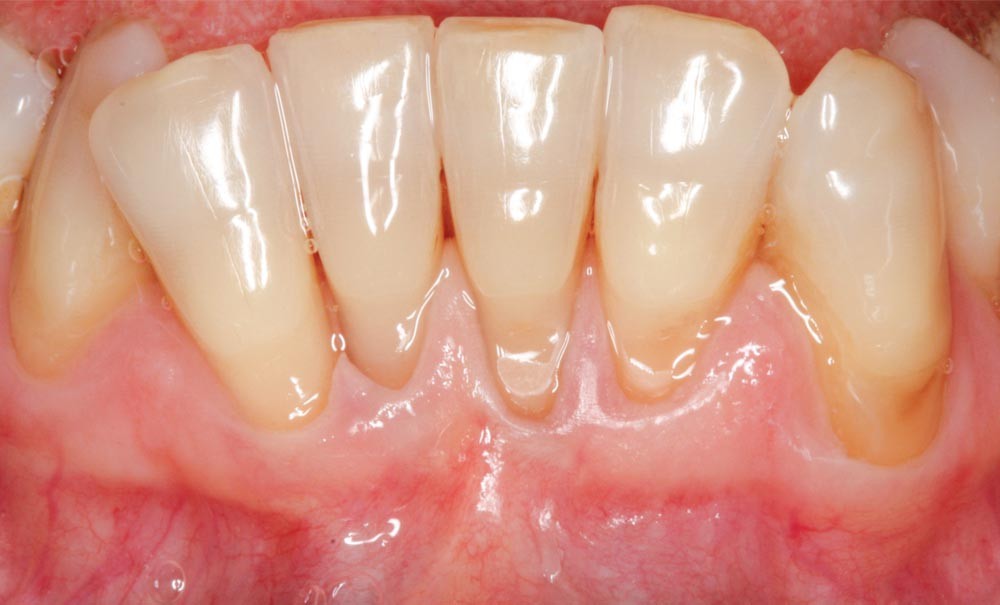

L’objectif de cet article est de présenter différentes approches thérapeutiques dans le secteur antérieur mandibulaire chez des patients présentant des récessions gingivales sévères associées à des pertes d’attache interproximale (RT 2 et 3 selon la classification de Cairo [3]).

Ces récessions sont associées à des paramètres cliniques dont la prise en considération avant toute thérapeutique est nécessaire. De plus, le choix d’une technique peut s’avérer difficile et l’apport de la littérature doit aider le praticien dans sa prise de décision. L’objectif de cet article sera de proposer trois approches thérapeutiques chirurgicales dans le secteur antérieur mandibulaire chez des patients présentant des récessions gingivales sévères associées à des pertes d’attaches interproximales (RT 2 et 3 selon la classification de Cairo), d’évaluer leurs résultats à six mois et leur cohérence avec les données publiées dans la littérature.

La récession gingivale se définit comme « la migration en direction apicale de la gencive marginale par rapport à la jonction émail-cément (JEC). Elle est associée à une perte d’attache exposant la surface radiculaire au milieu buccal » [1]. La région antérieure mandibulaire est une zone présentant fréquemment des récessions gingivales. Elles sont le plus souvent associées à un phénotype fin, au frein mandibulaire, à un vestibule peu profond et parfois à des pertes d’attache interproximale.

La chirurgie plastique parodontale aura pour objectifs d’améliorer l’environnement parodontal et de corriger les séquelles mises en évidence chez un patient présentant un parodonte réduit sain. L’expertise du praticien et les attentes du patient auront un impact sur la prise de décision chirurgicale [2].